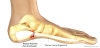

족저근막염의 이학적 검사

종골 안쪽돌기 바로 위와 근막을 따라 먼쪽 부위쪽 1~2cm 부위에 국소 압통을 호소합니다.

종종 체중부하 시 가해지는 정도의 압력을 주기 위해 강하게 눌러야만 압통이 나타나기도 합니다.

수동적으로 발가락을 신전시키면 통증을 악화될 수 있습니다.

아킬레스건이 긴장되어 있을 때도 있습니다.